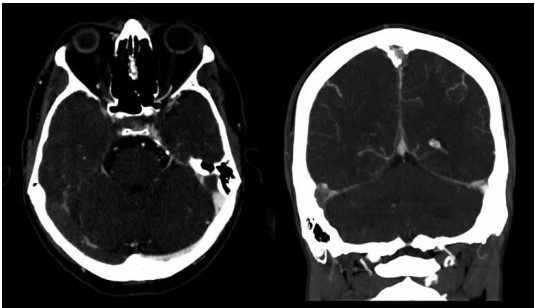

Paciente do sexo feminino, com 27 anos de idade, chega ao pronto-socorro com queixa de cefaleia refratária a analgésicos, com início há 2 dias. Foi submetida a tomografia computadorizada do crânio com contraste, conforme imagens a seguir:

(Arquivo pessoal; imagem usada com autorização)

Considerando as imagens apresentadas, assinale a alternativa correta.